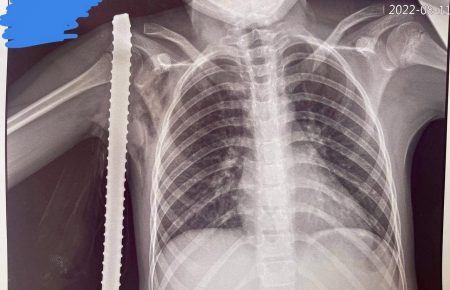

Франківські лікарі прооперували 10-річну дівчинку, яка впала на арматуру. ФОТО

Ввечері 11 серпня чергова зміна анестезіологів і хірургів обласної дитячої лікарні отримала непередбачувано цікавий клінічний випадок

Граючись на будівельному майданчику, десятирічна дівчинка випадково впала на арматуру. Наслідки могли бути трагічні, проте дитина відбулася наскрізною травмою м’яких тканин пахвинної ділянки, повідомляють медики Обласної дитячої лікарні.

В ургентному порядку дівчина доставлена в операційну, де була прооперована. Ранній післяопераційний період вимагав перебування пацієнта під спостереженням лікарів відділення інтенсивної терапії. На цю мить її життю та здоров’ю нічого не загрожує.